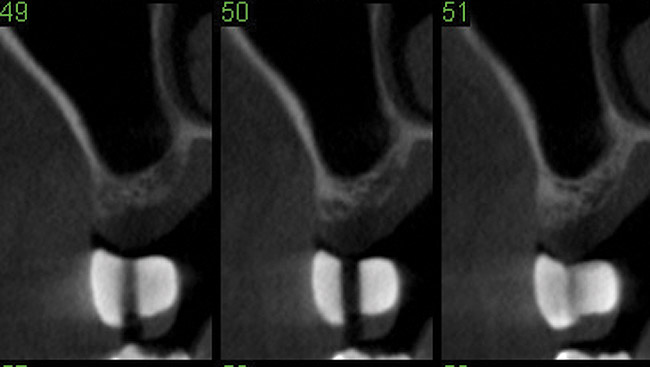

Fig 12. Cone-beam computed tomography 6 months after the procedure reveals the bony mantle covering the inserted implants.

Figure 12

Drill depth gauge—A common complication of the crestal drill osteotomy is unintended perforation of the Schneiderian membrane. As a consequence, specific sleeves in different lengths were developed (Figure 8). These sleeves, which are placed on the drills, serve as gauge stoppers that prevent drill overextension. While the Cosci system uses only 3-mm-diameter drills, the newer systems include wider-diameter drills, which offer better visibility and control of the osteotomy and the integrity of the Schneiderian membrane. Figure 9 shows an implant insertion case using one of the newer systems to perform this crestal osteotomy technique. Osteotomy was performed with a non-cutting drill in 1-mm depth increments using depth gauge stoppers until the bone tissue is removed and the intact Schneiderian membrane is visible. The Schneiderian membrane is then elevated using bone-filling material, as described by Summers’ original technique (Figure 10). Following sufficient augmentation, the implants are inserted (Figure 11). Cone-beam computed tomography after 6 months reveals the bony mantle covering the inserted implants (Figure 12).